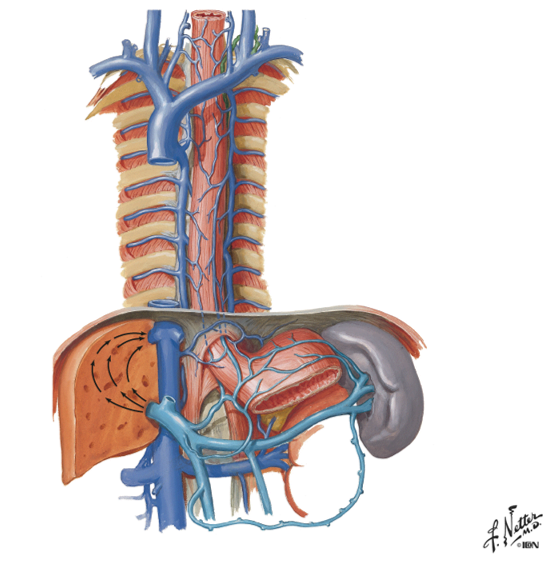

the intercostal spaces are drained via what?

via the intercostal veins

Intercostal veins drain __________ into azygos system and ________ into internal thoracic veins?

so overall the intercostal veins are coming back towards the center (arteries go out latterally) and go inside what?

posteriorly

anteriorly

the azygos vein

point out the azygos vein, the accesorry hemi-azygos vein and the hemi-azygos vein?

the azygos vein is on the right side under the big "faucet" going up

you can see a divit on the left side where the accessory hemi and hemi azygos travel behind and into the right side

the accessory hemi-azygos vein is the vein on the left side connecting the intercostal spaces from above the divit (on top)

the hemi-azygos vein is below the divit (on bottom)

overall, the "azygos system":

- drains what 2 things?

- consists of what 3 veins?

- “azygos system” also receives blood from where?

- this system acts as “collateral pathway” to “bypass” what?

the back & thoracoabdominal walls

azygos, hemi-azygos and accessory hemi-azygos veins

trunk and lower extremities

the IVC (inferior vena cava)

accessory hemi-azygos vein:

- receives blood from ______________ intercostal spaces

- Accessory hemi-azygos vein crosses midline and drains into where?

- NOTE: left side 1st – 4th intercostal spaces drain directly into where?

left side 5th - 8th

the azgos vein

left brachiocephalic vein

look at picture

hemi-azygos vein:

- receives blood from where?

- also receives blood from what other 2 left places?

- Hemi-azygos vein crosses midline and drains into __________?

left side 9th - 11th intercostal spaces

abdominal/pelvic trunk and lower extremity

azgos vein

look at picture

how is the lumbar veins a plan B?

they are a plan B in case there is some sort of obstruction in the inferior vena cava

(look at ascending lumbar vein in picture)

what do the right and left common illiac veins take care of?

the legs

azygos vein:

Receives blood from what 3 places?

Azygos veins continues on to drain into the ___________?

right side intercostals

hemiazygos & accessory hemiazygos veins

also receives blood from right abdominal/pelvic trunk and lower extremity

SVC (superior vena cava)

notice how it gets blood from the hemi azygos and accessory azygos and how it travels up into the SVC